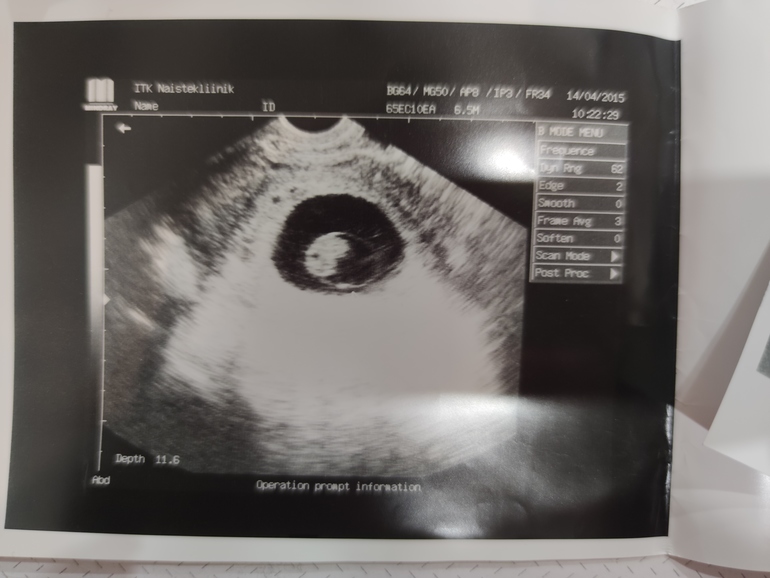

это мой младший сын :)

А так с хорошим походом!